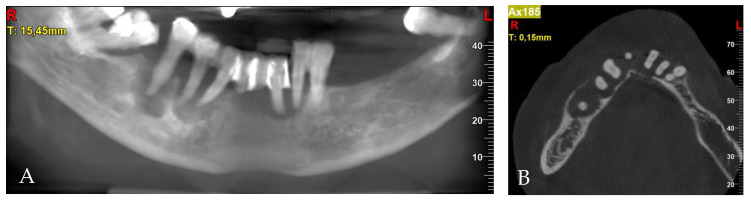

Pre-treatment CBCT: (A) panoramic view; (B) axial view; (C) cross-sections in position of teeth, respectively, 32; (D) 34; (E) 42; (F) 44; (G) 45; (H) 45.